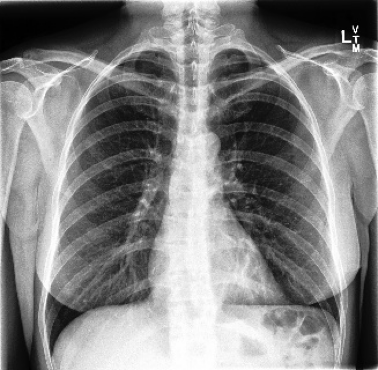

The availability of large public datasets and the increased amount of computing power have shifted the interest of the medical community to high-performance algorithms. However, little attention is paid to the quality of the data and their annotations. High performance on benchmark datasets may be reported without considering possible shortcuts or artifacts in the data, besides, models are not tested on subpopulation groups. With this work, we aim to raise awareness about shortcuts problems. We validate previous findings, and present a case study on chest X-rays using two publicly available datasets. We share annotations for a subset of pneumothorax images with drains. We conclude with general recommendations for medical image classification.